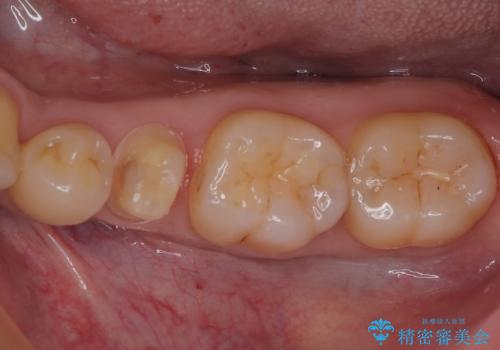

- 左下の奥歯のところがフロスが引っかかったり、ちぎれたりするとのことで来院された患者様です。検査の結果、神経は正常な反応を示し、フロスは引っかかる状態でしたので、虫歯治療も併せて行うためにオールセラミッククラウンによる補綴治療を行っていくことにしました。

拡大鏡視野下でプラスチックの詰め物、虫歯を除去しオールセラミッククラウンに適した形に整えました。